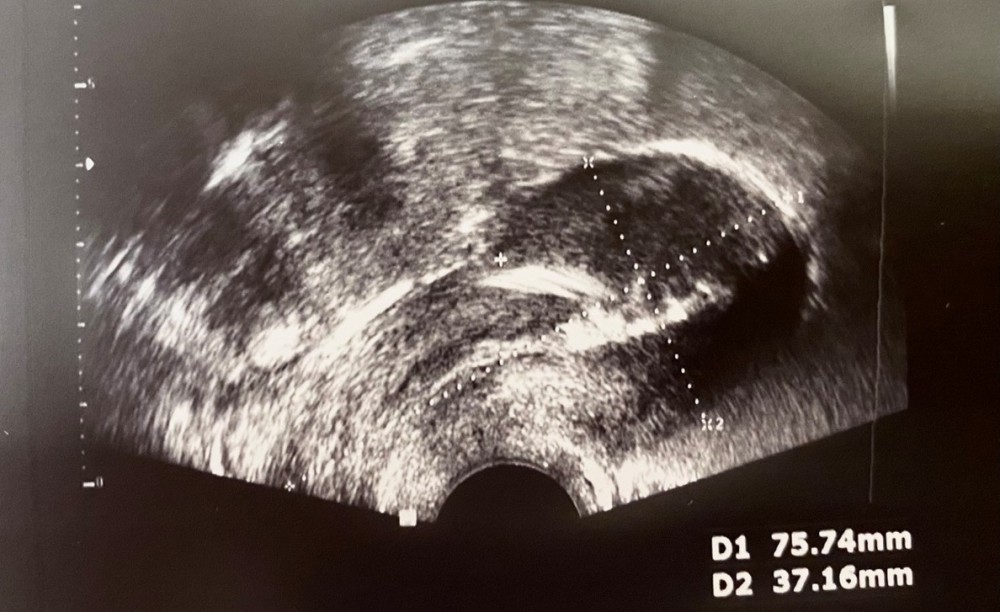

Část prezentace se věnovala IUD v ultrazvukovém obraze, viditelnosti jednotlivých typů a ultrazvukovému nálezu při nesprávném uložení tělíska.

Třetí kazuistika popsala případ ektopicky uloženého IUS v dutině břišní po dvou letech užívání metody, následnou diagnostiku uložení, laparoskopické odstranění a opětovné zavedení IUS na přání pacientky po hysteroskopické kontrole zhojení děložní stěny.